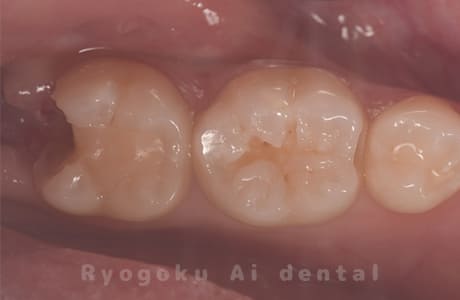

Case11

-

- 原因

- インレー2次カリエス、ならびにインレー脱離

- 治療内容

- セラミッククラウン、セラミックインレー

- 治療費用

- 123,000円×2(セラミッククラン)、77,000円(セラミックインレー)

銀歯が取れて、ご来院された患者様です。奥歯2本をセラミッククラウン、手前の小臼歯をセラミックインレーで治療を行いました。

<リスク・副作用>

過度の咬合や衝撃で割れることがあります。